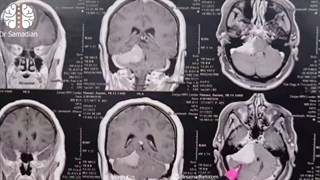

پخش صدا جراحی مننژیوم پتروکلایوال اشتراکگذاری لیست پخش ۰ نظر ۰ نظر دانلود دانلود ویدیو دانلود کیفیت 1080p ۱۱.۲۲ مگابایت دانلود کیفیت 720p ۶.۶۱ مگابایت دانلود کیفیت 480p ۴.۷۹ مگابایت دانلود کیفیت 360p ۳.۴۳ مگابایت دانلود کیفیت 240p ۲.۲۴ مگابایت دانلود کیفیت 144p ۱.۴۸ مگابایت گزارش تخلف بیشتر گزینههای بیشتر لیست پخش لایکها گزارش تخلف ۰ لایک دکتر محمد صمدیان منتشر شده در تاریخ ۱۴۰۰/۰۴/۰۲ این کانال دنبال شد دنبال کردهاید دنبال کردن این کانال دنبال کردن جهت کسب اطلاعات بیشتر به سایت دکتر صمدیان مراجعه کنید : https://drsamadian.com/ ادامه نظرات لبخند لبخند لغو ثبت نظری برای نمایش وجود ندارد.